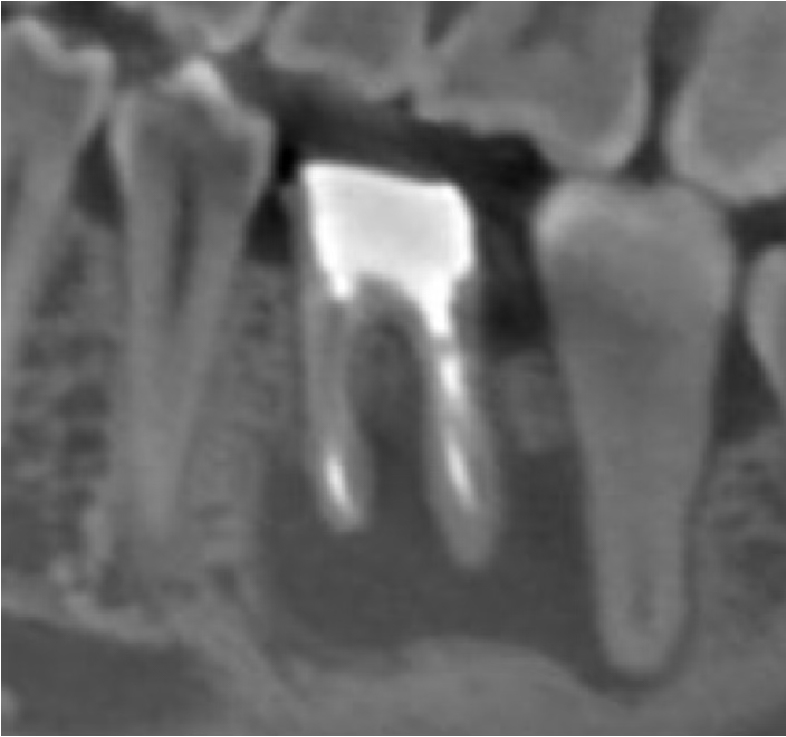

根管治療の症例

術前

術後2年4ヶ月

根管が大きく曲がっている歯は、器具操作が難しく、治療のために削る量が増えやすい傾向があります。本症例では、根管形態を正確に把握したうえで、湾曲根管に適した器具選択と精密な操作を行い、必要最小限の切削で根管治療(初回治療)を完了しました。

年齢性別 30代・女性

主訴 下の歯ぐきが腫れている

治療部位 左下3番

治療内容 初回根管治療(湾曲根管に対し、削る量を抑えた形成・根管充填の方針)

治療回数 2回

リスク副作用 治療後に痛みや違和感が出ることがあります。根管の形態によっては治療回数が増えたり、再治療が必要になる場合があります。

難しい形態ほど、治療結果は「勘」ではなく「手順と精度」に左右されます。歯内療法の専門医が担当することで、湾曲根管のような難易度の高いケースでも、歯質をできるだけ温存しながら、再発リスクを下げる治療を目指せます。